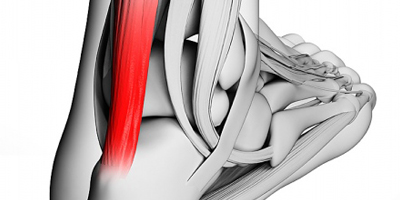

Rotura tendón de Aquiles

Rotura tendón de Aquiles La rotura del tendón de Aquiles sucede en cualquier rango de ...